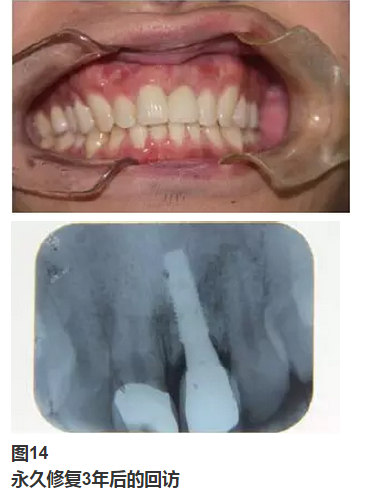

術(shù)前拍攝錐形束CT,進(jìn)行三維重建和種植方案規(guī)劃。從CT圖像中可以看出頜骨內(nèi)有骨島和殘根,為避免種植體植入骨島區(qū),考慮在兩側(cè)頦孔區(qū)種植4~5顆種植體,采用套筒冠進(jìn)行即刻修復(fù)。從重建的結(jié)果中可知前牙區(qū)牙槽嵴呈刀刃狀。種植方案為:對(duì)前牙區(qū)牙槽嵴進(jìn)行截骨修整,并在兩頦孔之間的區(qū)域內(nèi)植入5顆種植體。

圖15

種植方案的規(guī)劃:a.患者的CT圖像的截面圖,圈紅處為骨島;b.患者摘掉活動(dòng)義齒后的下頜;c.患者上下頜骨的CT三維重建;d.下頜骨截骨后模擬植入5顆種植體